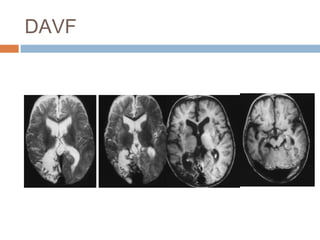

Hình ảnh DAVF: MRI

 Tín hiệu dòng trống xiang

quanh xoang màng cứng.

 Xoang màng cứng huyết

khối

 Dãn tĩnh mạch vỏ mà không

có nidus nhu mô

 T2W: tăng tín hiệu khu trú ở

nhu mô não kế cận

 MRA có thể âm tính

 MRV: tắc xoang màng cứng,

dòng bàng hệ